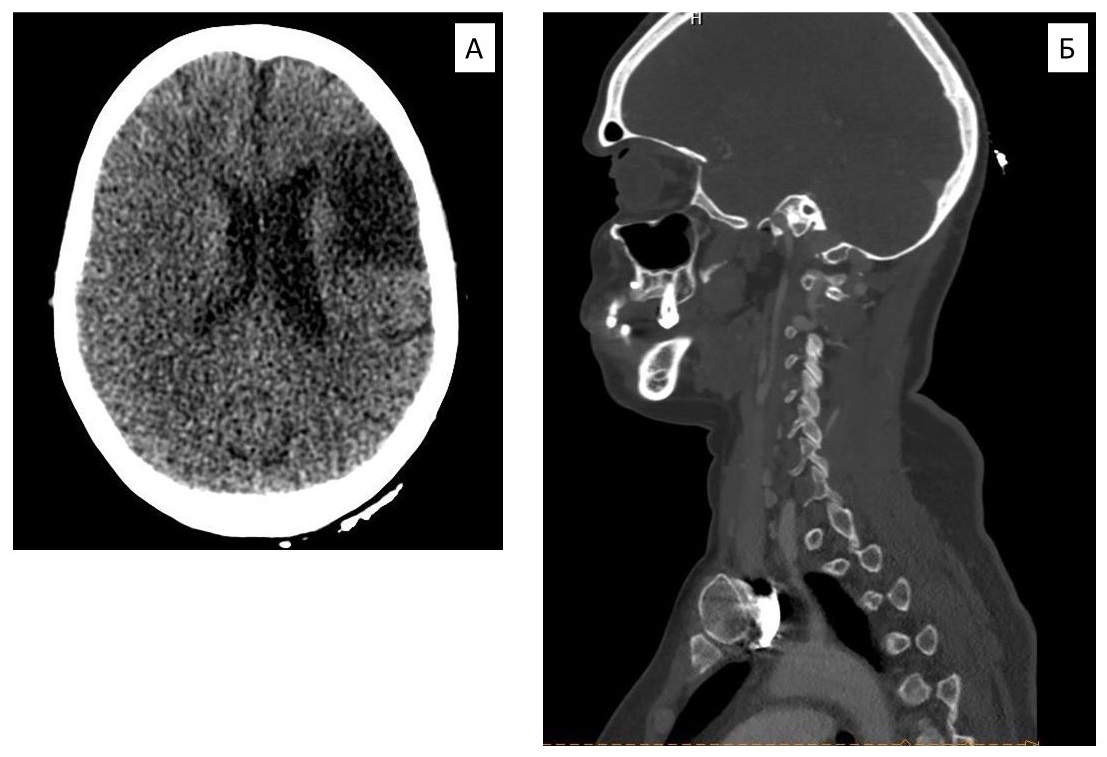

Gradually, the symptoms of the disease progressed, there was no constant monitoring, the patient did not receive treatment. She was examined again on an outpatient basis in 2019, occlusion of both CCAs was revealed (Figure 1). In the previous 6 months, she noted progression of cerebral symptoms in the form of unsteadiness of gait. There was also a tendency to arterial hypertension, antihypertensive therapy was selected at the place of residence, the target blood pressure level was achieved. DS of the brachiocephalic arteries (BCA) detected 90% stenosis of the left subclavian artery (SA), occlusion of the right SA. No lesions of the descending and abdominal aorta, of the visceral branches of the aorta, and of the arteries of the lower limbs were detected.

Fig. 1. Computed tomography of brachiocephalic arteries and the brain of the patient before surgical intervention (2020): cystogliotic alterations of the left frontal lobe (A); occlusion of the common carotid artery (B).